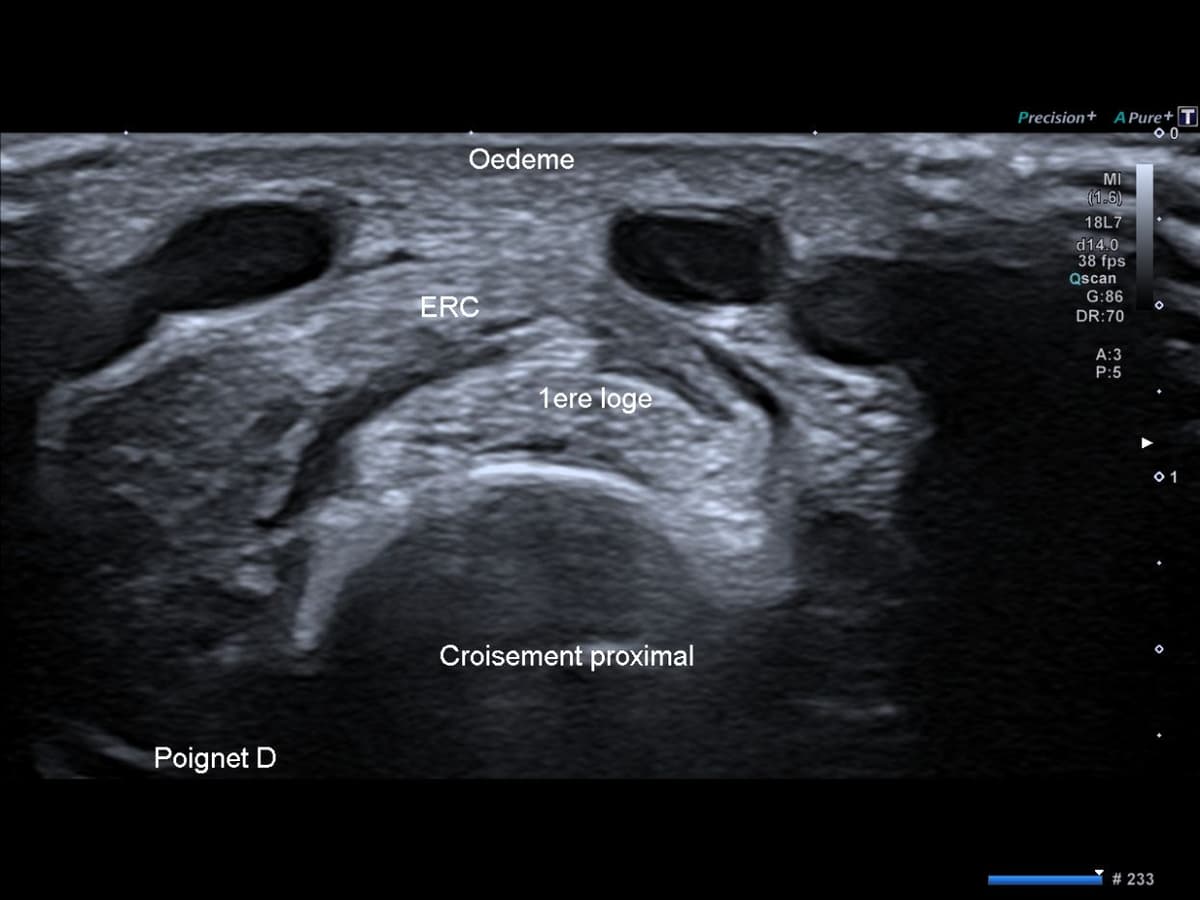

Syndrome du croisement proximal

Syndrome du croisement proximal de l'avant-bras

Douleur distal de l'avant-bras chez un jeune patient livreur de course à domicile.

US